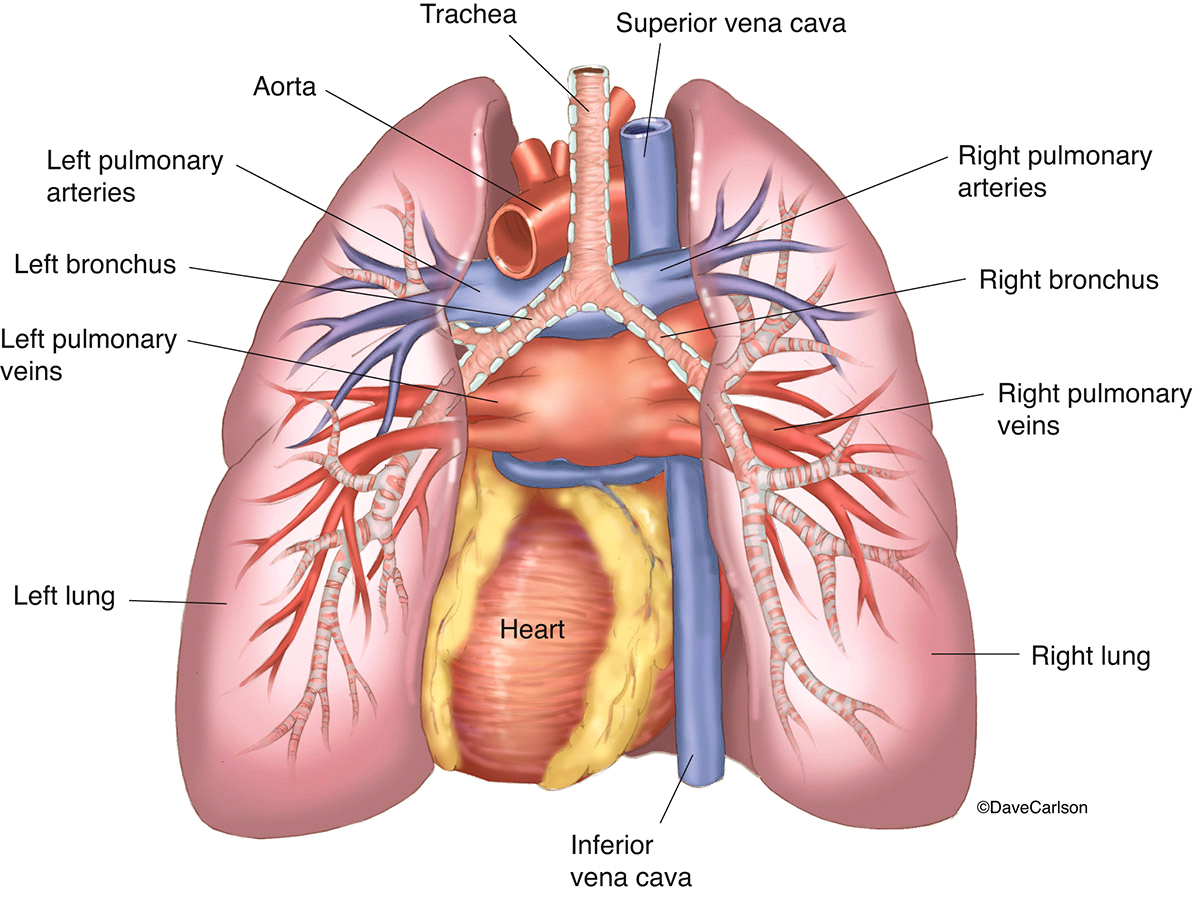

Анатомия Сердца: Расположение и Функции